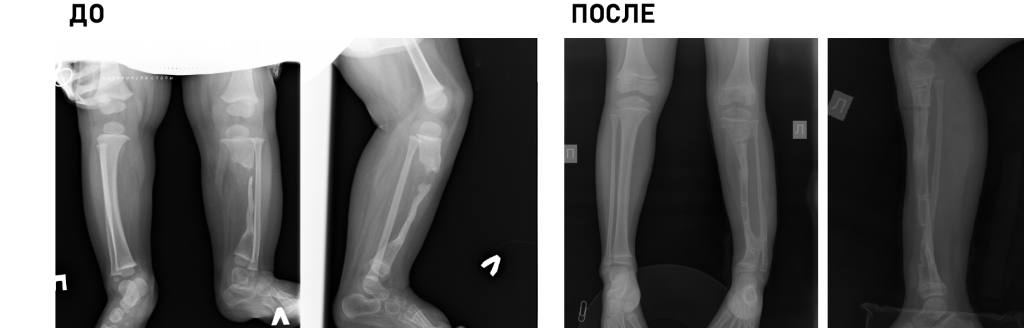

Клиника является единственным медицинским учреждением Российской Федерации, выполняющим полный комплекс диагностических и лечебных мероприятий у детей с деструктивными поражениями любых отделов скелета, в т.ч. малоинвазивные биопсии, иммунологические исследования, гистологическую и бактериологическую верификацию.

Основной принцип работы: обязательный учет возрастных особенностей ребенка и потенциал его роста.

Технические возможности: технологии малоинвазивной (MIS) и реконструктивной хирургии, костнопластические материалы и инструментальная фиксация, современное силовое и ультразвуковое операционное оборудование, навигация, нейромониторинг.